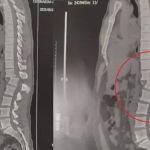

Daniel Diau acabou gravando o próprio acidente enquanto se exercitava com uma barra de ferro

O equipamento estava balançando enquanto o homem fazia o exercício e, em seguida, tombou

O jovem tentava erguer 70 kg em um exercício mas deixou a barra cair e morreu no local